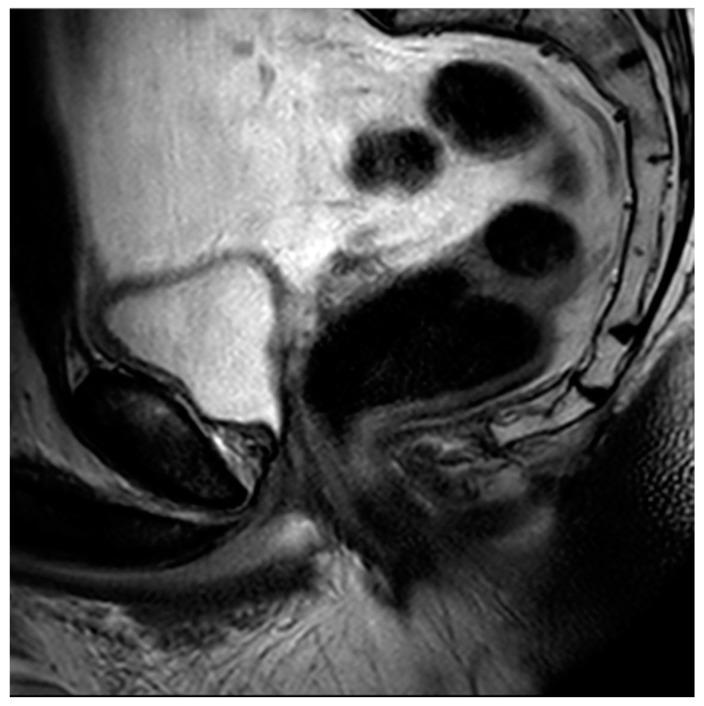

Contemporary Review of Multimodality Imaging of the Prostate Gland.

Tissue changes and the enlargement of the prostate, whether benign or malignant, are among the most common groups of diseases that affect men and can have significant impacts on length and quality of life. The prevalence of benign prostatic hyperplasia (BPH) increases significantly with age and affects nearly all men as they grow older. Other than skin cancers, prostate cancer is the most common cancer among men in the United States. Imaging is an essential component in the diagnosis and management of these conditions. Multiple modalities are available for prostate imaging, including several novel imaging modalities that have changed the landscape of prostate imaging in recent years. This review will cover the data relating to commonly used standard-of-care prostate imaging modalities, advances in newer technologies, and newer standards that impact prostate gland imaging.